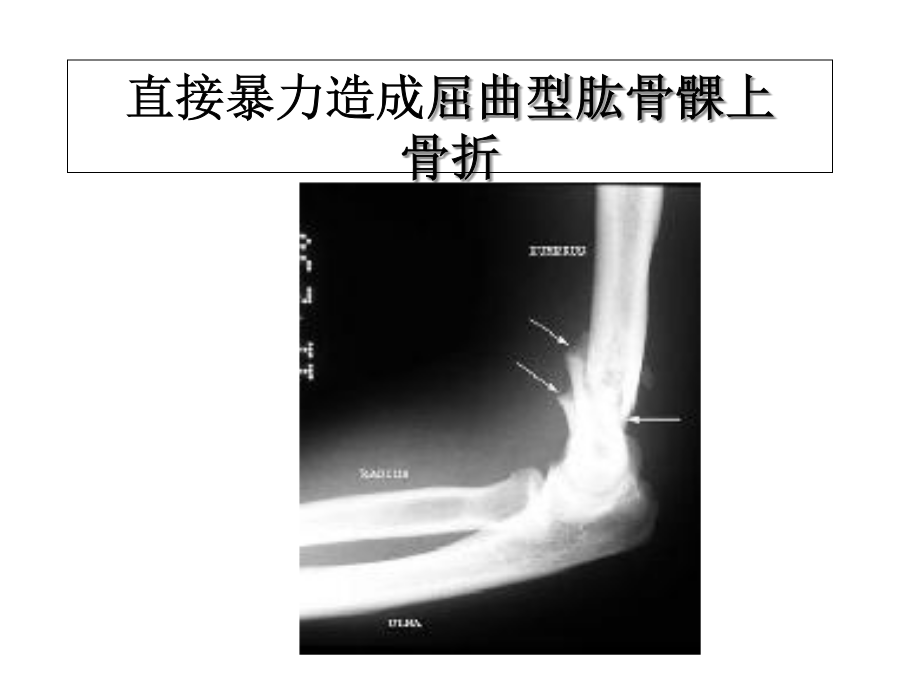

骨折概论医学知识讲座一、定义二、成因1.直接暴力直接暴力造成屈曲型肱骨髁上骨折2.间接暴力间接暴力造成伸直型肱骨髁上骨折3.积累性劳损4.骨骼疾病骨质疏松,轻微外力造成股骨粗隆间骨折三、分类闭合性骨折开放性骨折不完全骨折完全骨折粉碎性骨折稳定性骨折不稳定性骨折骨骺骨折四、骨折段移位(远端相对于近端)原发移位多与外力方向相符 继发移位受肌肉牵拉影响明显 如股骨骨折移位明显且不稳定五、临床表现1.畸形桡骨远端骨折,背侧移位,称Colles骨折,餐叉样畸形股骨颈骨折,下肢外旋、缩短2.异常活动3.骨擦音或骨擦感4.局部疼痛压痛5.肿胀和瘀斑6.活动障碍7.全身表现六、X线检查七、常见并发症1.脂肪栓塞综合征(1)表现(2)处理2.骨筋膜室综合征(1)骨筋膜室(2)病理(3)早期表现(4)晚期表现—5p’s(6)后果很严重!(7)防治3.关节僵硬持续被动功能锻炼八、骨折愈合过程1.血肿机化演进期(约骨折后2周)2.原始骨痂形成期(通常4~8周)3.骨痂改造塑型期(约需8~12周)4.影响骨折愈合的因素治疗方法的影响:股骨颈骨折、股骨头血供破坏,易发生骨不连或缺血坏死胫骨中下段骨折,损伤滋养动脉,血供不足,愈合慢九、骨折急救1.ABC’s2.检查神经血管功能股骨下段骨折腘动脉受压手、足的运动检查手、足的感觉检查肱骨中段骨折损伤桡神经,产生垂腕腓骨头骨折损伤腓总神经,足下垂3.包扎伤口、控制出血4.临时固定5.转运十、治疗骨折的原则1.复位(1)手法复位复位后需检查复位情况,观察肢体外形,抚摸骨折处的轮廓,与健侧对比,并测量患肢的长度,即可了解复位后的大概情况。 X线透视或摄片检查,可进一步正确肯定复位的情况。(2)持续牵引复位骨牵引用不锈钢针穿过骨质,通过牵引弓、绳子及滑车进行牵引。根据需要,调整牵引重量及方向,重量一般用体重的1/7~1/8,对位后要减重量保持对位。牵引时间也可延长到2~3月,适用于一切有移位的成人骨折。 常用的牵引部位有上肢的尺骨鹰咀,尺、桡骨下端,指骨远端;下肢为股骨髁上,胫骨结节,胫骨下端及跟骨。脊柱骨折可行头颅牵引。 (3)手术切开复位解剖复位功能复位的标准2、固定外固定(externalfixation)2)石膏外固定3)持续牵引(皮牵引、骨牵引):可用于复位,也可用来固定,方法及特点在前已述。 牵引的指征: ①股骨闭合性骨折。 ②股骨、胫骨开放性骨折。 ③已感染的开放性骨折。 ④颈椎骨折或脱位。应用牵引时,必须注意按病人年龄、性别、肌肉发达程度及软组织损伤的情况,随时调整牵引的重量,即要达到复位和固定的目的,又要防止过牵和畸形愈合。 内固定3.功能锻炼(1)早期阶段(2)中期阶段(3)晚期阶段骨折临床愈合标准骨折临床愈合时间运动系统解剖生理概要1.骨胳skeleton2.骨胳肌3.关节关节类型谢谢聆听!